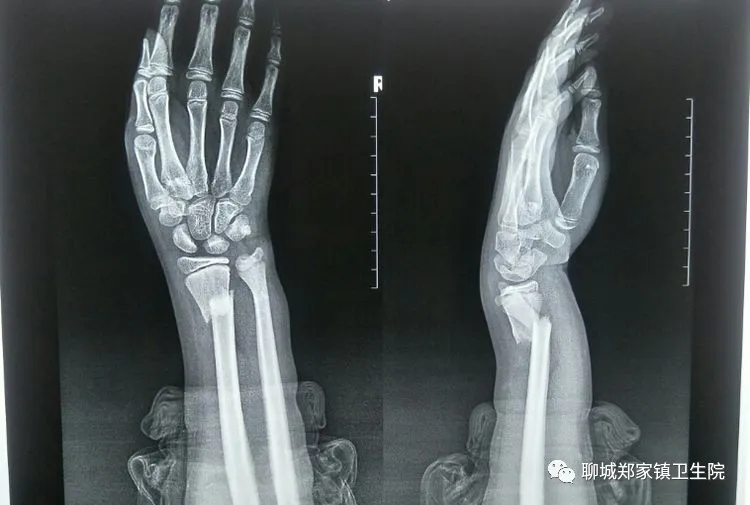

日前,家住冠县的11岁小患者任某某,就读于聊城市城区内学校,因上体育课时摔到,伤及左前臂,老师联系家长后,家长从冠县赶往聊城,遂即来我院郑家院区骨科检查,x线片示左尺桡骨双骨折,骨科主任吕士金检查阅片后,当即决定给予中医正骨手法复位小夹板外固定,复查整复后x线片示骨折端对位对线良好,向病人交待注意事项及指导功能锻炼后,病人遂即返回学校继续上课,定期逢周末来我院复查。